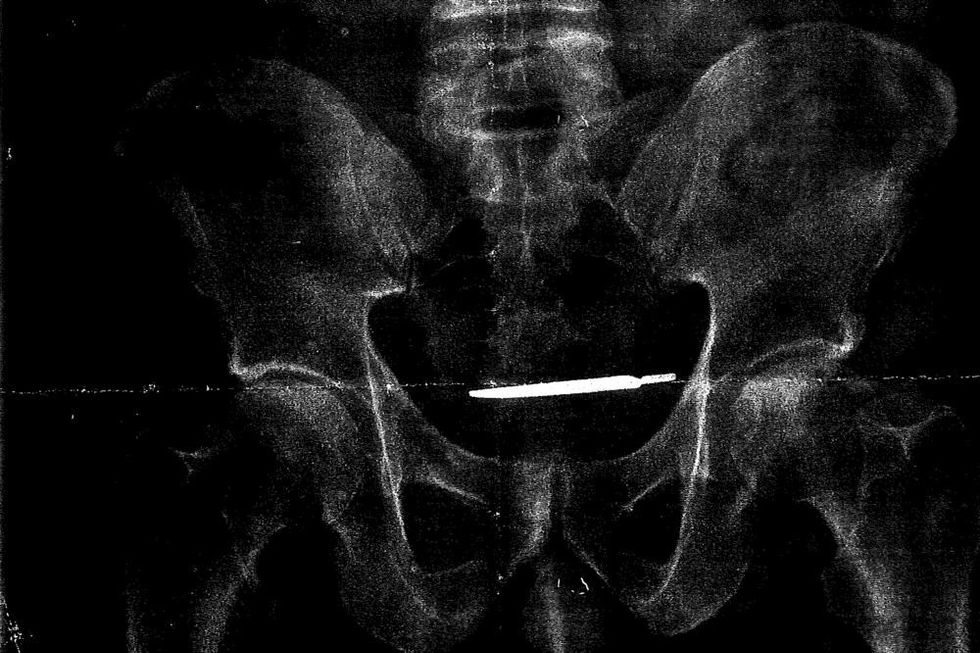

Për katër vite duroi dhimbjet e mëdha në bark, ultrazëri ia zbuloi bisturin që i kishte mbetur gjatë operacionit që e kreu në 4 vite më parë (Foto)

Pas dhimbjeve të mëdha në bark që i kishte pasur për shumë vite, veterani i ushtrisë amerikane ka zbuluar se në bark i kishte mbetur një bisturi gjatë operacionit që i është nënshtruar në spitalin ushtarak në Konektikat.

Dhe pasi që ka bërë ultrazërin, mjekët kanë pasur çfarë të shohin. Aty ata ia kumtuan lajmin se duhet t'i nënshtrohet edhe një ndërhyrje tjetër kirurgjike, për t'ia nxjerr nga barku bisturin që i kishte mbetur në bark para 4 viteve.